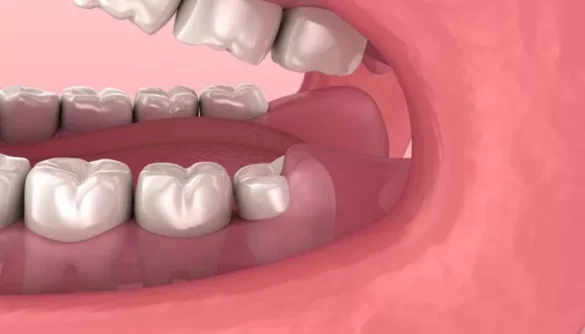

Molars are large, flat teeth located at the back of your mouth. They play a crucial role in chewing and grinding food. When molars begin to grow, especially during late childhood or early adulthood, many people experience discomfort or pain. This pain can be mild, moderate, or even severe in some cases. Understanding why molars hurt during growth is essential for managing symptoms and maintaining good oral health.

The discomfort associated with growing molars often occurs during the eruption of these teeth, particularly wisdom teeth.

The gums must stretch and open to allow the teeth to emerge, which can result in swelling, inflammation, and pain.

One of the primary causes of molar pain is inflammation of the gums. As the tooth breaks through the gum tissue, it can irritate the area. This inflammation often results in swelling, tenderness, and a throbbing sensation.